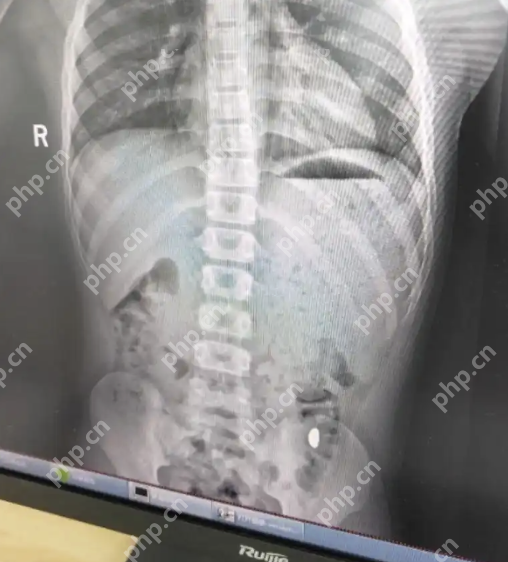

4、医院的门诊病历单清楚地显示,经过检查后,诊断结果为“胃内有异物”,影像中右下角的亮点,正是那颗失踪了五天的金豆子。